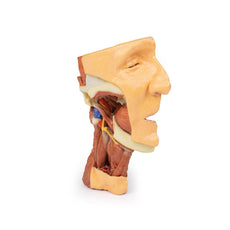

The head and neck of the specimen provides views of both superficial and deep structures in the region. The calotte has been removed ~2cm superior to the orbits to expose the brain in relation to the endocranial cavity. The transverse section through the cerebrum demonstrates the relation of the grey matter cortex to the white matter medulla, as well as the lateral ventricles with a small amount of choroid plexus visible in the base of both spaces. The skin and superficial fascia on the right side has been retained and false-coloured to display the angiosomes of the face and posterior neck. On the left side, the superficial tissues have been dissected to expose the muscles of facial expression, muscles of mastication, and deeper structures of the infratemporal fossa including the lingual nerve, terminal branches of the external carotid artery into the superficial temporal and maxillary arteries.

The carotid sheath has been opened on both sides of the neck, and the internal jugular veins and sternocleidomastoid muscles largely removed, to expose the pathway of the common carotid arteries, internal and external carotid arteries, and the vagus nerves. On the right side, the great auricular nerve ascends towards the face, while the hypoglossal nerve can be seen adjacent to the exposed stylohyoid ligament and supra- and infrahyoid muscles. A large thyroid gland is present bilaterally inferior to the thyroid cartilage, with a well-preserved superior thyroid artery and inferior thyroid vein on the right side and across the midline.

The head and neck of the specimen provides views of both superficial and deep structures in the region. The calotte has been removed ~2cm superior to the orbits to expose the brain in relation to the endocranial cavity. The transverse section through the cerebrum demonstrates the relation of the grey matter cortex to the white matter medulla, as well as the lateral ventricles with a small amount of choroid plexus visible in the base of both spaces. The skin and superficial fascia on the right side has been retained and false-coloured to display the angiosomes of the face and posterior neck. On the left side, the superficial tissues have been dissected to expose the muscles of facial expression, muscles of mastication, and deeper structures of the infratemporal fossa including the lingual nerve, terminal branches of the external carotid artery into the superficial temporal and maxillary arteries.

The carotid sheath has been opened on both sides of the neck, and the internal jugular veins and sternocleidomastoid muscles largely removed, to expose the pathway of the common carotid arteries, internal and external carotid arteries, and the vagus nerves. On the right side, the great auricular nerve ascends towards the face, while the hypoglossal nerve can be seen adjacent to the exposed stylohyoid ligament and supra- and infrahyoid muscles. A large thyroid gland is present bilaterally inferior to the thyroid cartilage, with a well-preserved superior thyroid artery and inferior thyroid vein on the right side and across the midline.